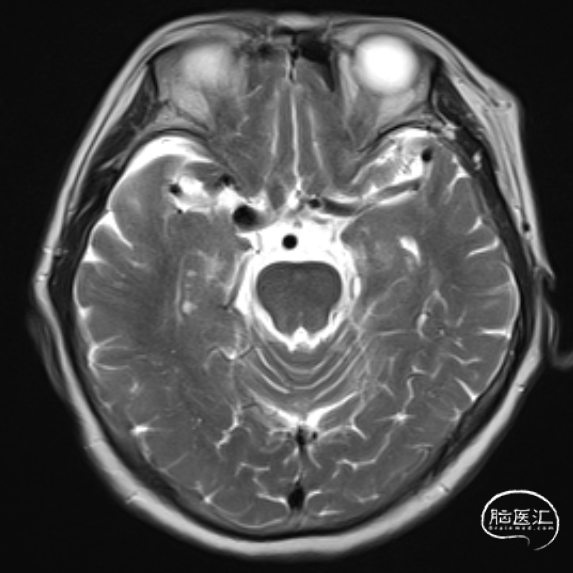

MRI:

简要病史:患者近2周前体检行核磁MRI检查发现右侧颈内动脉动脉瘤,进一步完善头颅CTA检查明确为右侧颈内动脉C7段动脉瘤。